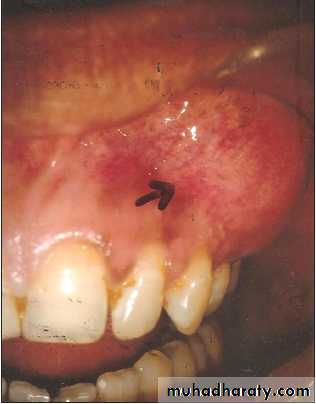

Ameloblastoma:-

It is a tumor arising from embryonal cells of developing teeth. Although most forms of this tumor simulate other slow-growing benign tumors some can develop malignant tendencies.Patient may have few subjective symptoms during tumor growth. Enlargement of the tumor may expand the buccal, lingual or palatal bone plates. Tooth may be loosen and pressure symptoms may occur.

Raioraghical examination may demonstrate unlocular or multilocular types. Unilocular ameloblastomas may be confused with benign cysts. The tumors frequently absorbs the alveolus surrounding ,the roots of teeth and may absorb root ends.

Ameloblastoma grow by extension into adjacent tissues and may perforate the investing bone. A biopsy should precede treatment since

these tumors frequently present with individual characteristics.